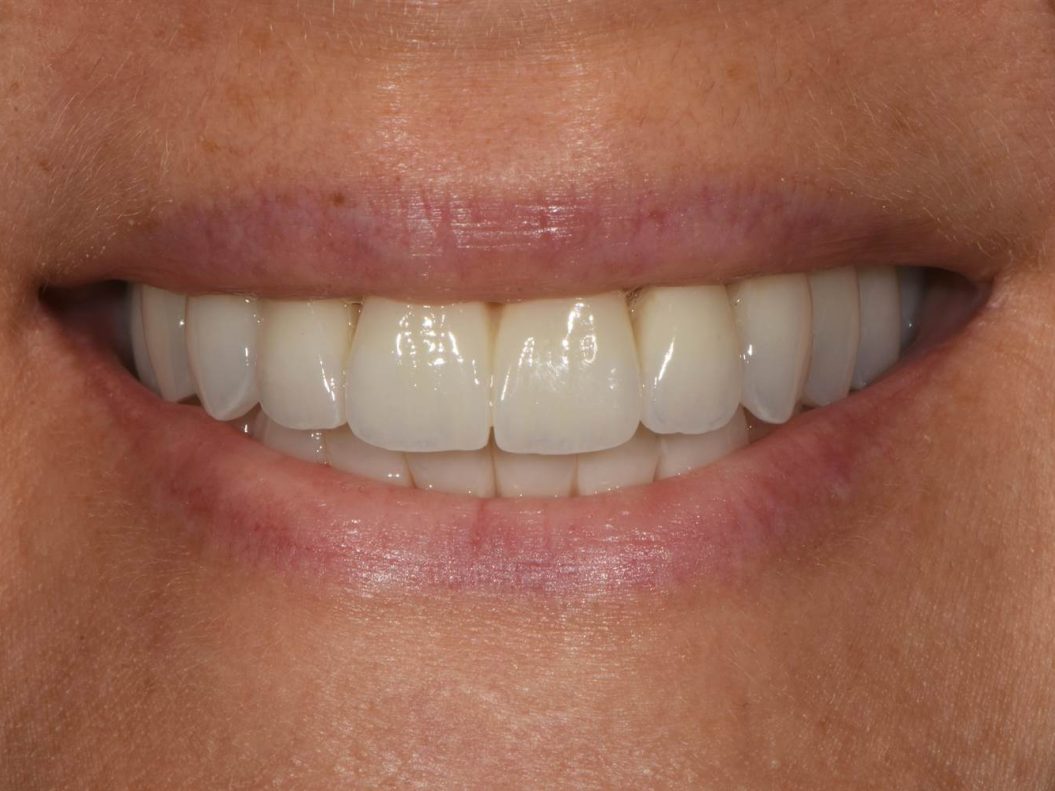

Un sorriso che cambia tutto – l’esperienza della nostra paziente dopo la terapia All-on-4®

Nella galleria fotografica seguente potete vedere la trasformazione del sorriso – si tratta di una paziente reale della nostra clinica, a cui sono stati inseriti i nuovi denti in poche ore.

- Fotografie finali del nuovo sorriso